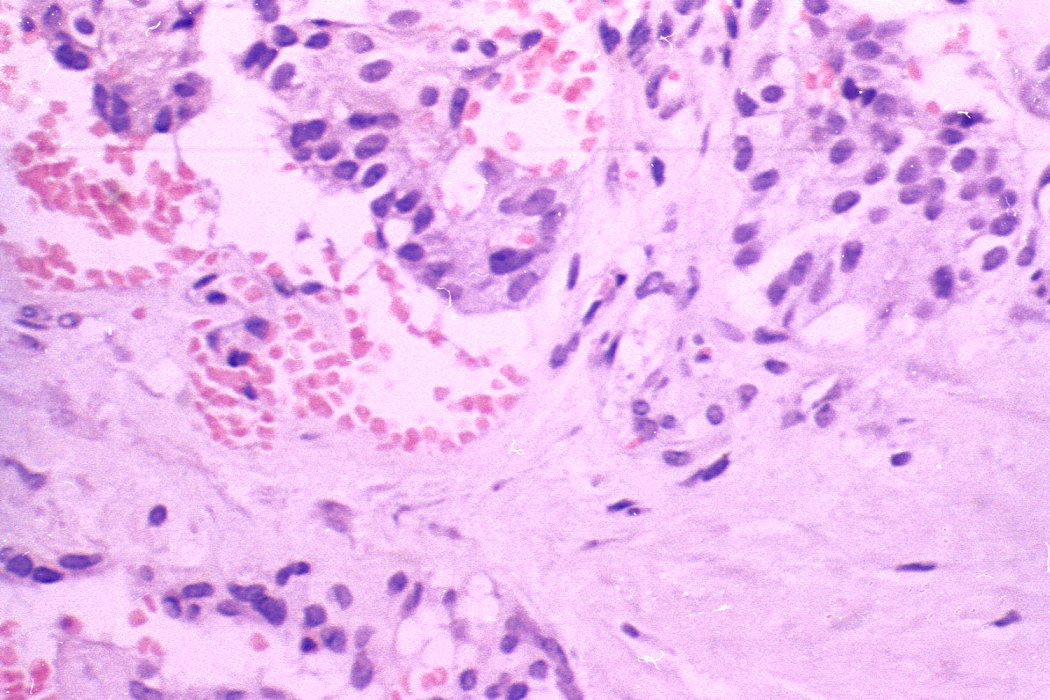

Thyroid cancers - case 174 (histologic picture 4)

H.E.-section, 400x. The previously demonstrated vessel is filled with tumor cells.